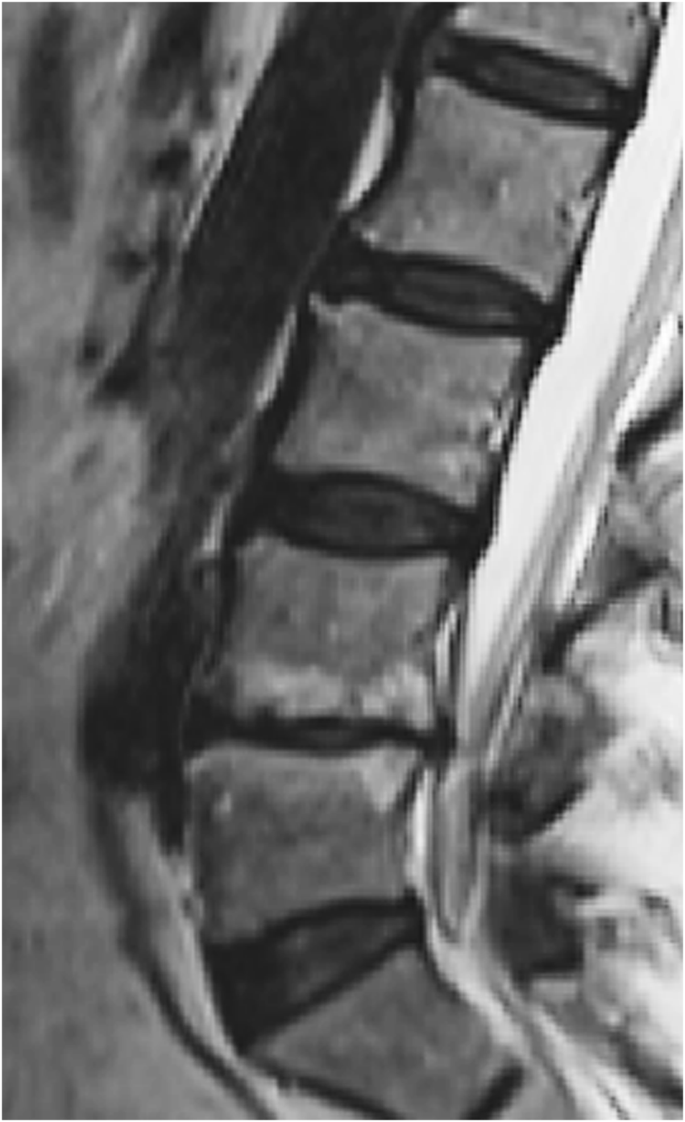

In a clinical study with 1-year follow-up, MC type 1 was associated with both decreasing the disc height and increasing the size of endplate defects17. In another longitudinal clinical study sample DD, endplate defects and MC were found to be significantly associated with each other. Endplate defect grade ≥4 was found to be a risk factor for both DD and MC progression, with MC being the last MR feature to develop in this process18. All these results seem to build on the same line of thoughts (Fig. 4).

MRI scan showing endplate defect grade VI both at the L4/L5 rostral and caudal endplates, with associated Modic changes (MC) over both rostral and caudal bone marrows adjacent to endplates and disc degeneration evaluated as Pfirrmann grade 5. As the endplate is a fundamental part of the vertebral body-endplate-intervertebral disc motion segment, one could consider endplate defects to be an initiating factor not only for disc degeneration, but also for MC. MRI indicates magnetic resonance imaging. From Rade M, et al. Vertebral endplate defect as initiating factor in intervertebral disc degeneration: Strong association between endplate defect and disc degeneration in the general population. Spine 43, 412–419 (2018). With permission.